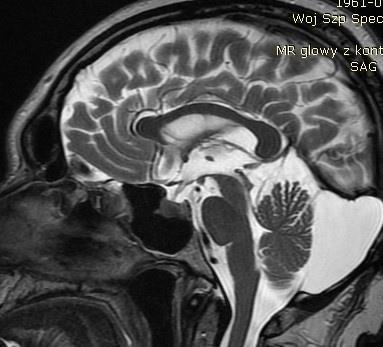

Pytanie 71

Zdjęcie przedstawia jeden z przekrojów strzałkowych w badaniu rezonansu magnetycznego głowy. Struktury wskazane strzałkami odpowiadają lokalizacji: